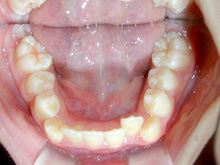

知多市大興寺在住 I.A様(女性)

I.A様は上下の前歯の歯並びがガタガタの叢生が主訴で来院されました。

矯正相談で叢生の場合には歯を移動させ整えるにはスペースが必要で、

スペースの獲得には抜歯の必要性をお話した後、診断のための資料採取をおこないました。

診断の結果、側貌(プロファイル)が良好なため抜歯を行なうことなく治療ができることをお伝えしました。

了解を得られましたので診断時にお渡しした治療計画書を提出してもらい、治療を開始することにいたしました。

上下顎の前歯に叢生(ガタガタ)がみられ、歯列弓の狭窄もすこしあります。臼歯関係は1歯対2歯です。

上顎歯列弓をQ.H(クワドヘリックス)という拡大装置にて拡大します。

処置方針どおり抜歯を行なうことなく、動的治療が完了しました。

非抜歯で治療した場合には後戻りに叢生の傾向がみられます。

動的治療を終了しても少なくとも動的治療に費やした年月は保定が必要です。